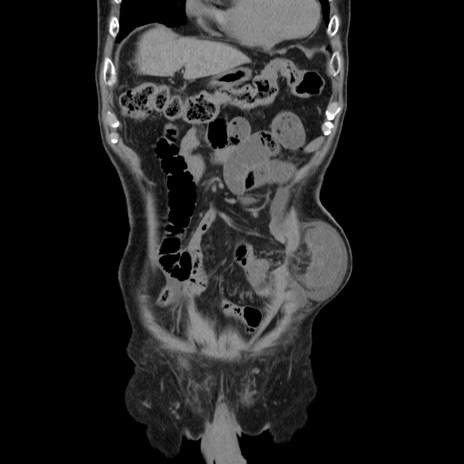

症例24(冠状断像)

【身体所見】意識清明、BT 35.9℃、BP 221/93mmHg、SpO2 97%(RA) 、腹部:左ストーマ周囲に限局性の腹部膨隆あり。 膨隆部自発痛・圧痛あり・軟。